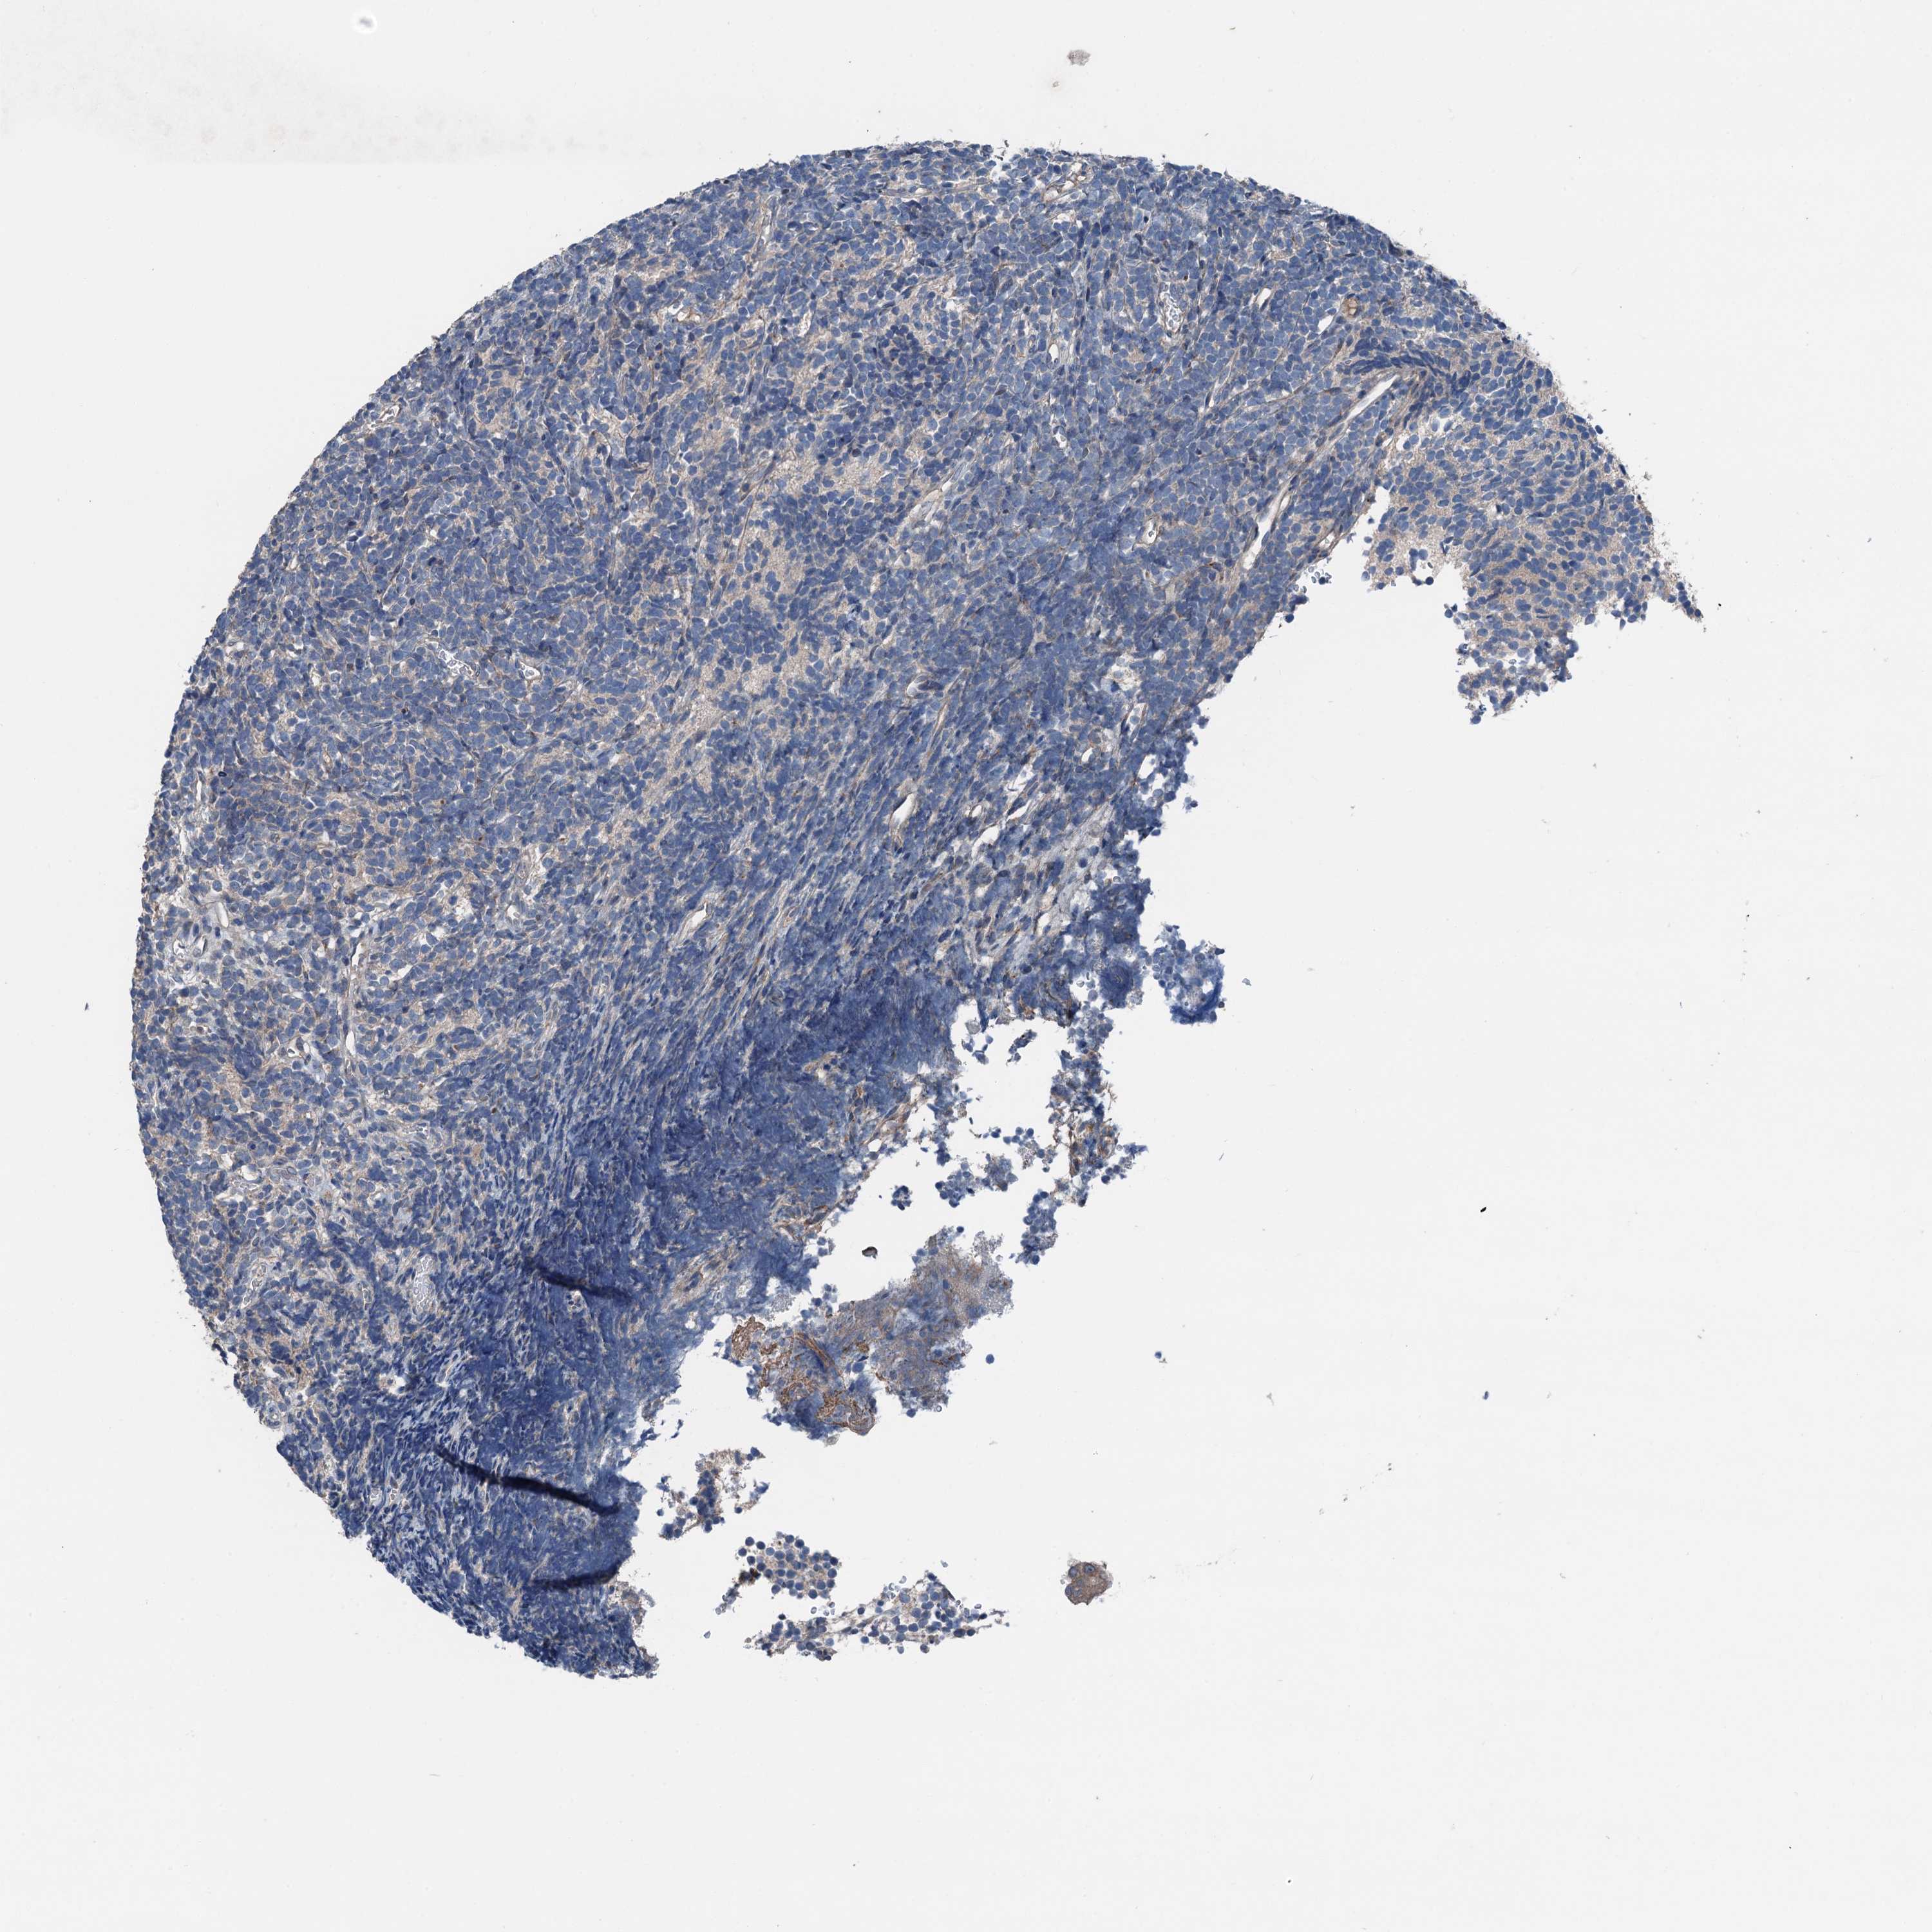

GLIOMA - Protein expressioni

A mouse-over function shows sample information and annotation data. Click on an image to view it in a full screen mode. Samples can be filtered based on level of antibody staining by selecting one or several of the following categories: high, medium, low and not detected. The assay and annotation is described here.

Note that samples used for immunohistochemistry by the Human Protein Atlas do not correspond to samples in the TCGA dataset.

Antibody stainingi

Antibody staining in the annotated cell types in the current human tissue is reported as not detected, low, medium, or high, based on conventional immunohistochemistry profiling in selected tissues. This score is based on the combination of the staining intensity and fraction of stained cells.

Each image is clickable and will lead to virtual microscopy that enables deeper exploration of all samples and also displays staining intensity scores, fraction scores and subcellular localization as well as patient and tissue information for each sample.

Antibody HPA041015

Staining

High

Medium

Low

Not detected

Intensity

Strong

Moderate

Weak

Negative

Quantity

>75%

75%-25%

<25%

None

Location

Nuclear

Cytoplasmic/membranous

Cytoplasmic/membranous,nuclear

Glioma, malignant, High grade

Glioma, malignant, Low grade